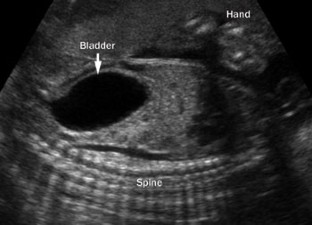

Robyr, R. et al. Correlation between ultrasound and anatomical findings in fetuses with lower urinary tract obstruction in the first half of pregnancy. Ultrasound Obstet. Gynecol. 25, 478–482 (2005).

Bernardes, L. S. et al. Keyhole sign: how specific is it for the diagnosis of posterior urethral valves? Ultrasound Obstet. Gynecol. 34, 419–423 (2009).